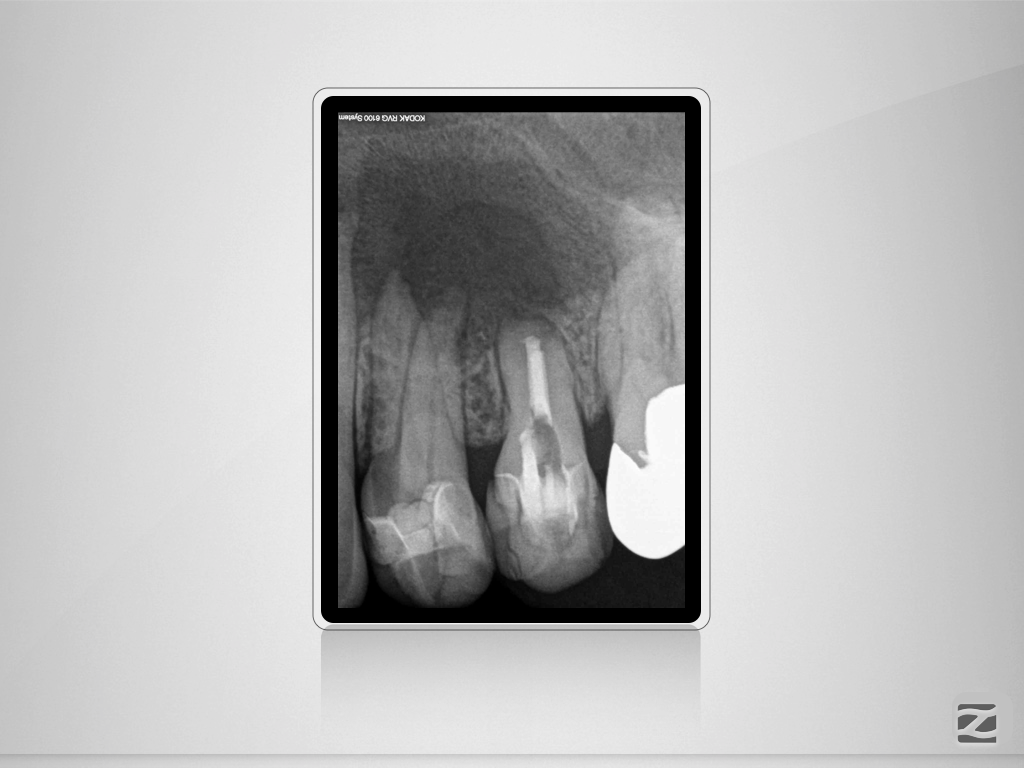

24D.001

Große Aufhellung, langes Recall